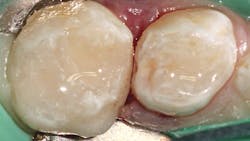

A selective-etch technique with 35% phosphoric acid is used to achieve the highest possible bond strengths.6,7 The etchant is washed and the tooth is dried without desiccating it. A universal bonding agent (Futurabond U, Voco) is rubbed onto the tooth surface for 20 seconds (figure 3), and thenThis is a modified snowplow technique, in which the flowable base layer is light cured in combination with placement of 4 mm of the restorative material.8,9 This allows the flowable to extrude up to the occlusal surface and down to the gingival margins, filling any voids.

The restorative material is warmed first in a Caps WarmerNano-ORMOCER materials provide clinicians with an excellent restorative option for pediatric patients that can appease concerned caregivers without disrupting current workflows. No doubt public scrutiny of our restorative materials will continue, whether their conclusions are legitimate or ill-informed. But we will also continue to see children with dental caries, so we would do well to add new materials to our armamentarium that can support good oral health outcomes and reassure caregivers of their safety.